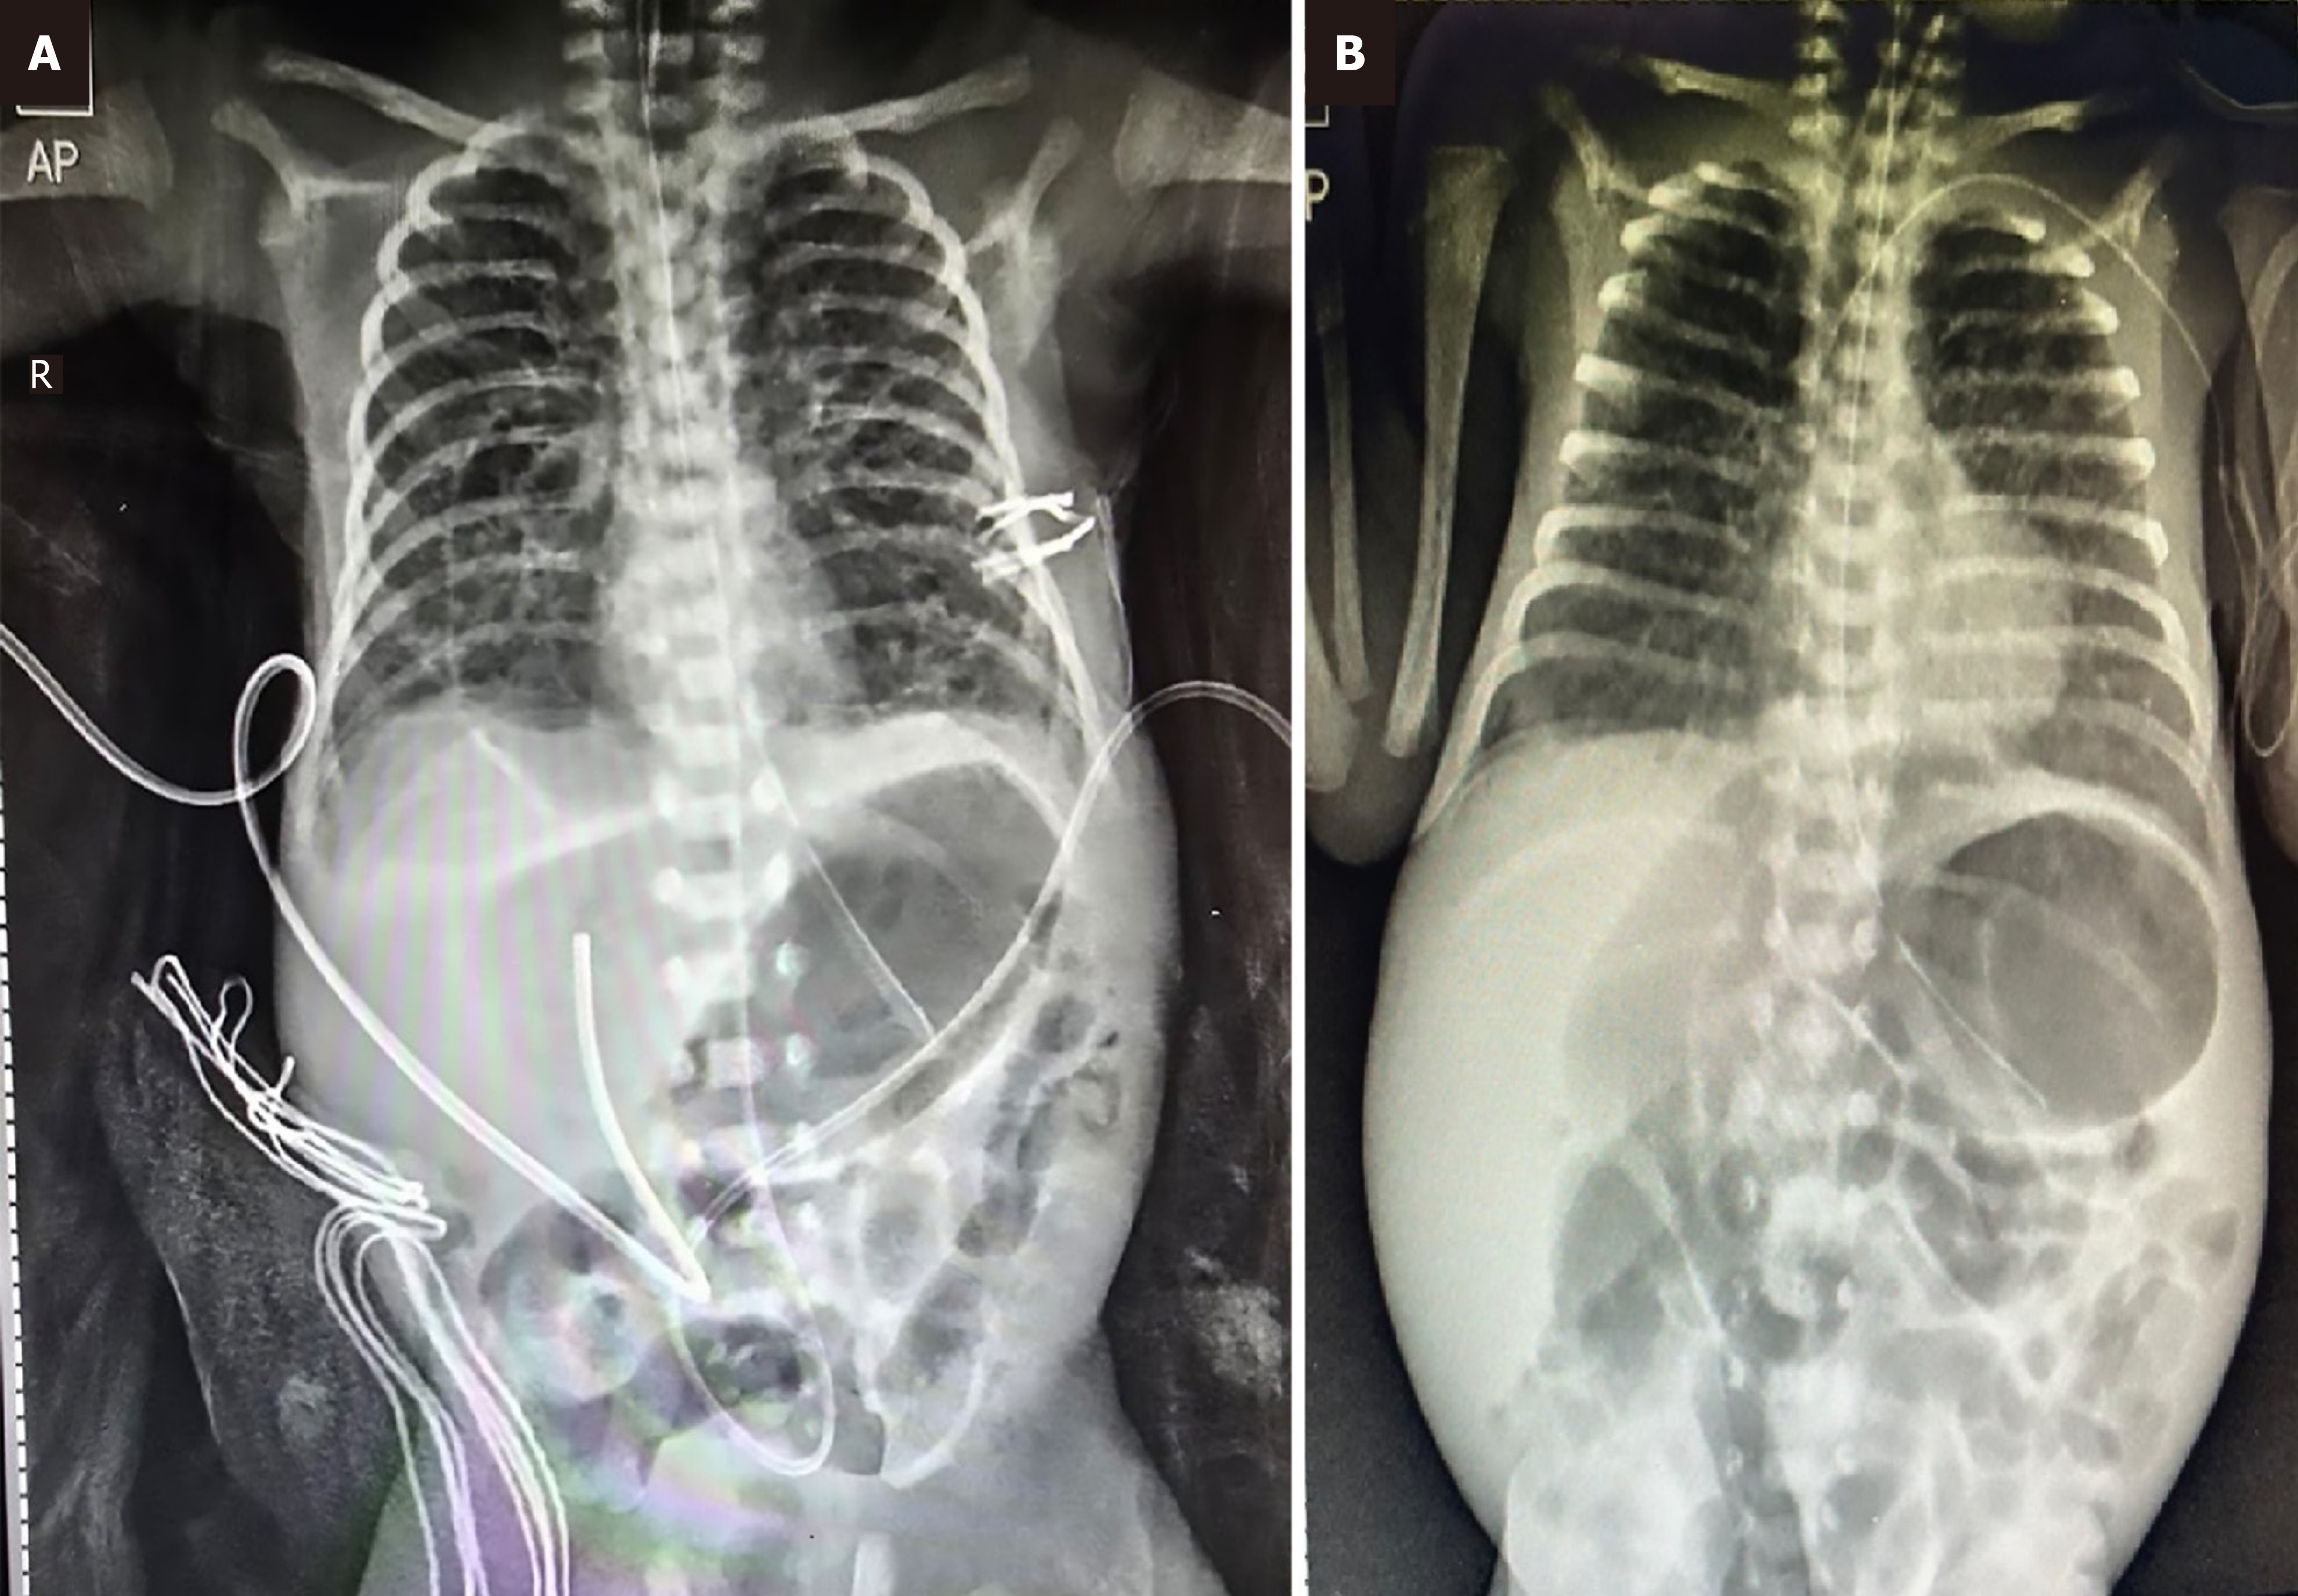

Figure 2 Chest and abdominal radiograph.

A: Chest and abdominal radiograph (anteroposterior view) obtained on day 8 of life, showing the migrated umbilical venous catheter positioned within the liver. The radio-opaque gauze pieces were placed at the site of the peritoneal drain on the right iliac region; B: Chest and abdominal radiograph (anteroposterior view) shows central position of the peripherally inserted central catheter with improvement in bowel gas pattern after removal of the umbilical venous catheter.